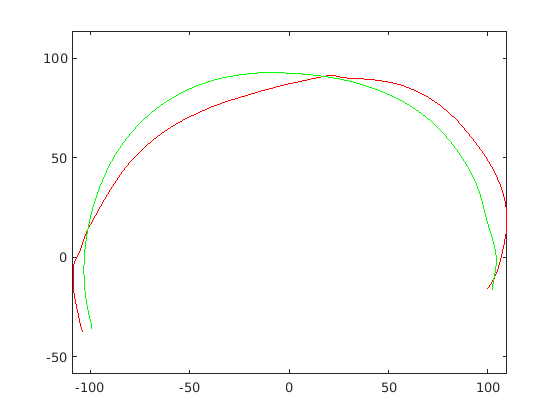

For each of the three segments, we determine the range of gradients on that segment by simple differencing between consecutive points. Each segment is rotated into a 2D frame such that maximum absolute values of positive and negative gradients are equal. Cubic spline contours are fitted to the three profiles and the head profile contour is reconstructed using the three individual cubic splines. Fig. 14 show examples of these.

|

|

|

|